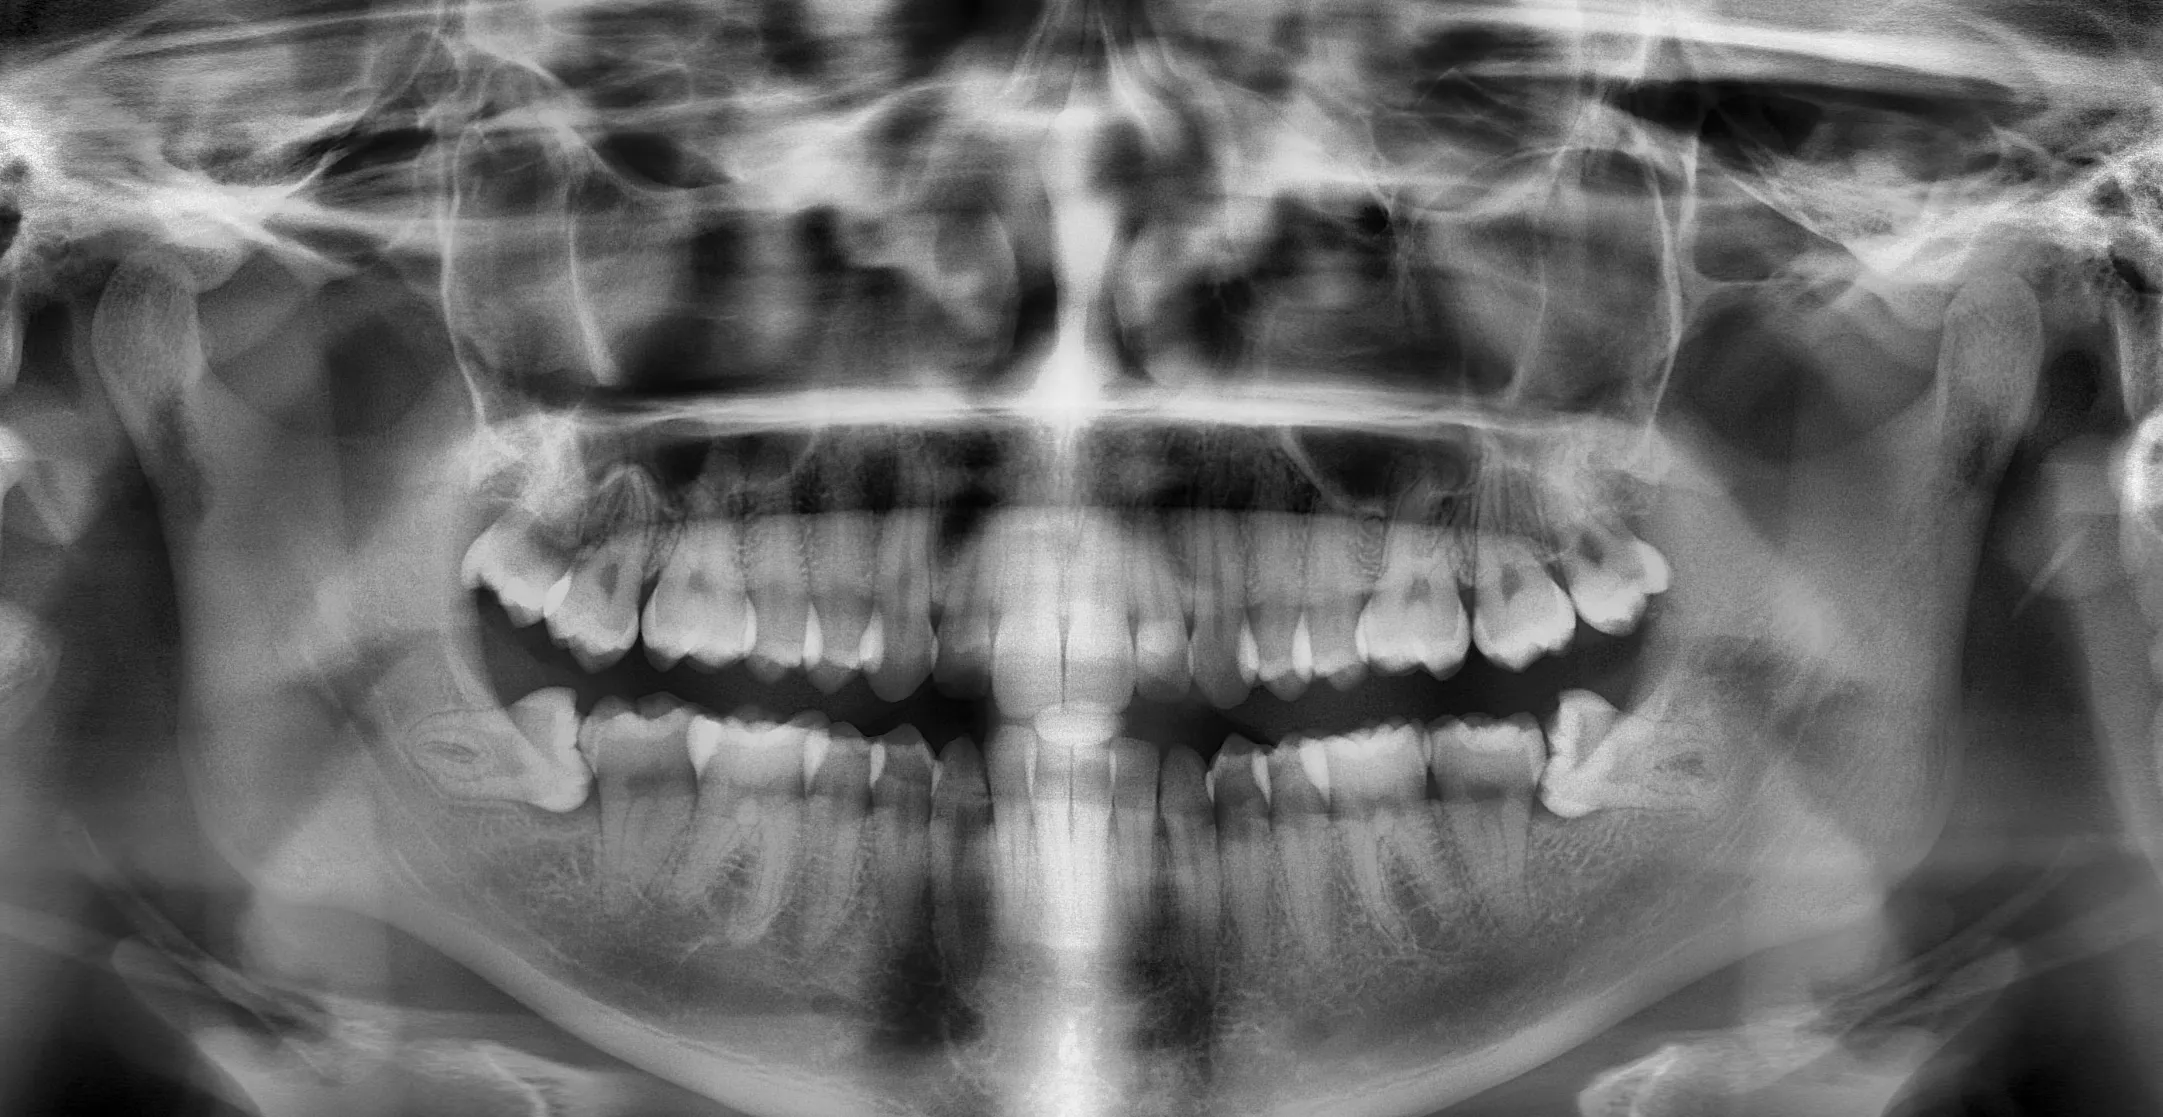

Hallazgos detectados

Caries oclusal visible en pieza 36

AltaPosible resorción radicular en pieza 46

MediaImagen radiopaca en seno maxilar derecho

BajaiAngela describe los hallazgos visibles en la imagen. El diagnóstico y la decisión clínica siempre quedan en manos del profesional.

Interpretá radiografías en segundos

Subí el estudio de imágen y obtené un resumen estructurado de los hallazgos visibles, listo para revisar con tu equipo clínico.

Clasificación automática

Reconoce panorámicas, periapicales, seriadas y CBCT, y organiza los hallazgos por región de la boca.

Hallazgos con nivel de confianza

Cada observación se reporta con un puntaje claro: alta, media o baja. Sin vueltas, sin falsa certeza.

Describe, nunca diagnostica

iAngela detalla lo que se ve en la imagen y el profesional mantiene siempre el criterio clínico.